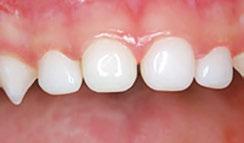

Kidstown Dental often consults for “re-treat” on poorly done or reattached tongue ties. Dr. Amy shares a sweet email from a patient who had received a frenectomy in another practice with a laser that does not use water and works with heat. The family came to Dr. Amy months after the surgery, thinking they needed a second surgery because the child was still suffering with feeding, speech, and sleep. Dr. Amy did three of the non-surgical treatments of LAFTR paired with interdisciplinary bodywork and functional help, and they were able to achieve life-changing results without any further surgery. Now, he is 3 years old and is sleeping and eating normally and speaking in full sentences. Dr Amy shares, “Only a few years ago, this child would have likely ended up with multiple surgeries, increasing the risk of scar tissue, oral aversions, and trauma, and still end up in a variety of therapies, like speech and occupational therapy. I am so glad we can finally help families with this simple, elegant, yet powerful laser intervention.”

Dr. Amy explains how to avoid a surgery if the child has signs of tongue tie and even the look of a posterior tongue tie. “Sometimes a frenum can look short and tight, and the patient may present with a lot of tongue-tie symptoms, but it may not actually be a true physical restriction. LAFTR is a great tool to use for differential diagnosis, particularly of posterior tongue tie. For example, the genioglossus muscles are airway dilator muscles under the tongue, and the frenum lays just over these muscles with lots of fascia connected to and around it. When patients have an airway issue, their genioglossus muscles are going to be contracting to dilate that airway open, and the frenum will be necessarily shortened artificially. So a short frenum on the initial exam may be indicative of an airway challenge. When the patient’s frenum is cut, the body will generally form the new frenum to be just as short and tight as the previous frenum, and then it often gets classified as ‘reattached.’ But LAFTR instantly releases all the artificial tension in the fascia, making it supple, and sometimes the frenum will lengthen 2-3 times compared to how it appeared on initial exam. A true physical restriction of the lingual frenum doesn’t lengthen because the fibers of a true tongue tie are different from simple fascia in a normal frenum. This is why we use this tool prior to any non-reversible cutting procedures.”